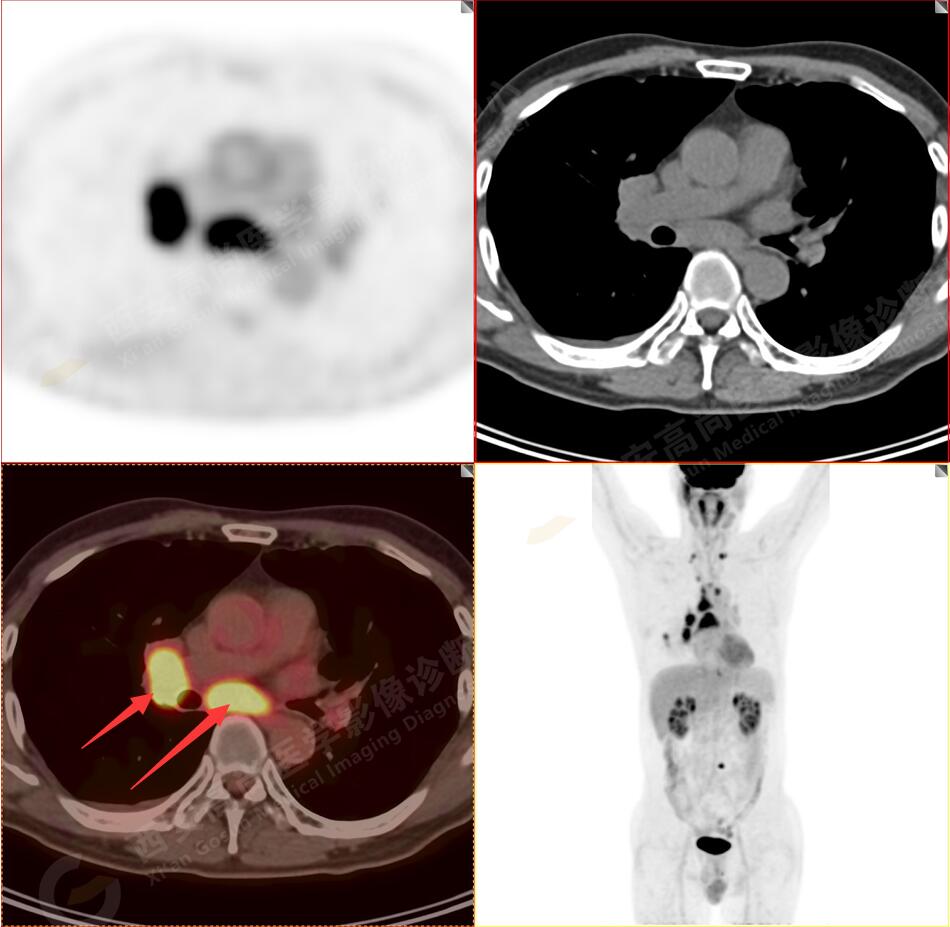

2.以下為全身多發(fā)轉移灶

3.右側肺門、縱隔(1L、1R、3A、4、6、7組)及雙側鎖骨上多發(fā)腫大淋巴結,呈不同程度FDG代謝異常增高,考慮為淋巴結轉移。

4.右后胸膜輕度增厚,形成多個條狀軟組織病變,呈FDG代謝輕度異常增高,考慮為轉移性病變;右側胸腔微量積液。

5.腰4椎體左側緣溶骨性骨質破壞,FDG代謝異常增高,考慮骨轉移瘤。

以上病變符合:T4N3M1c,ⅣB期(UICC/AJCC,2018年第8版肺癌TNM分期)。